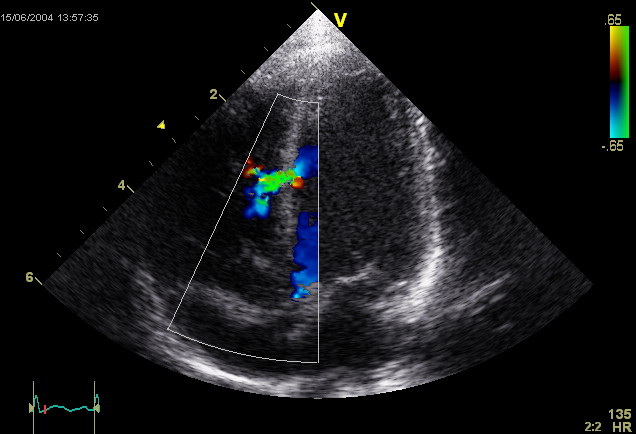

Существует несколько методов диагностики, которые позволяют выявить наличие патологического отверстия между желудочками:

- электрокардиограмма;

- эхокардиография;

- ультразвуковое исследование сердца;

- рентгенография;

- пульсоксиметрия;

- магнитно-резонансная томография грудной клетки.

При необходимости врач может назначить зондирование полостей сердца, что позволяет определить уровень кислородного насыщения и измерить давление после закрытия клапанов. Эти данные помогают составить точный прогноз и оценить риски, связанные с возможной операцией.